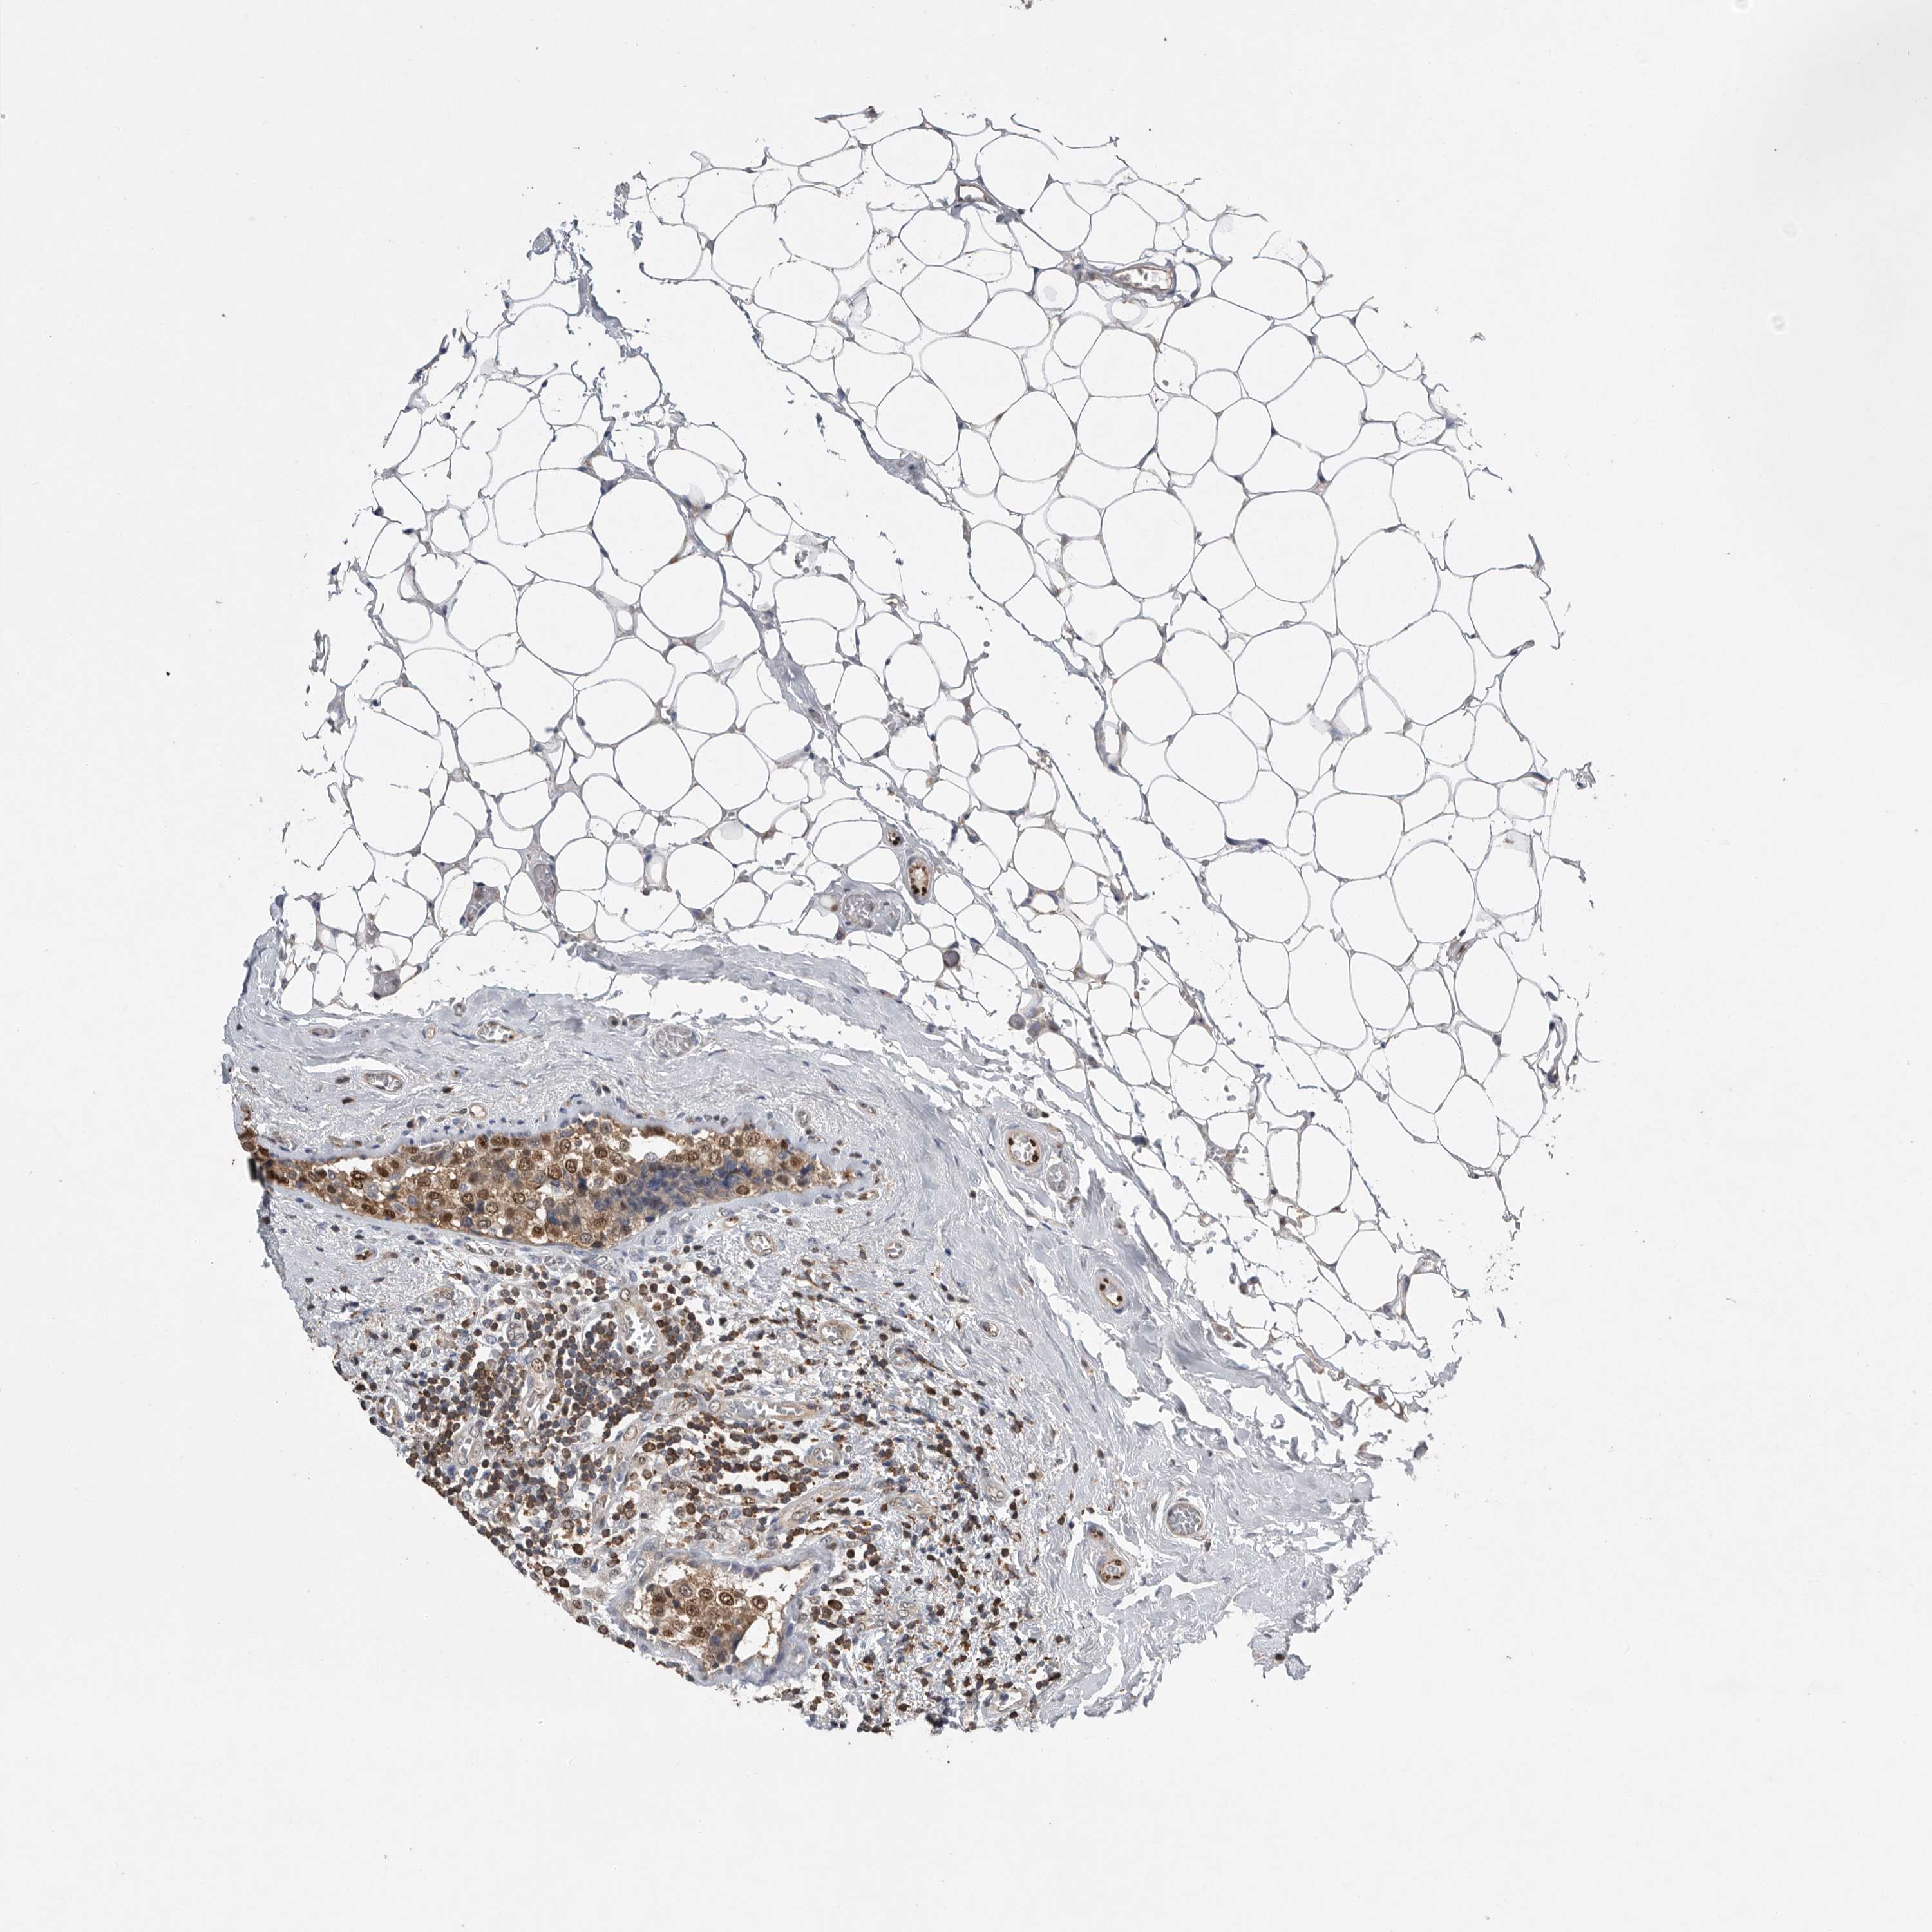

CANCER BREAST CANCER Show tissue menu

BRCA TCGA BRCA VALIDATION PROTEIN EXPRESSION